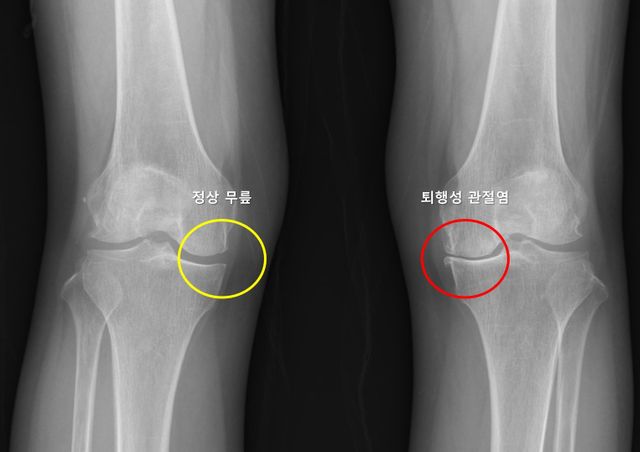

▲ 사진제공=서울대학교병원

무릎 퇴행성 관절염은 연골의 점진적인 손상과 관절 구조물의 퇴행성 변화로 인해 발생하는 질환으로, 통증과 운동 제한을 유발하며 삶의 질을 크게 저하시킬 수 있다. 전 세계 인구의 약 16~30%에서 발생하며, 고령화 사회로 접어들면서 그 유병률은 꾸준히 증가하는 추세다. 많은 환자들이 한쪽 무릎에 관절염이 생긴 뒤 수년 내 반대쪽 무릎에서도 통증이나 구조적 변화가 나타나는 경험을 하지만, 이러한 양측성 진행이 모든 환자에게서 동일하게 나타나는 것은 아니며, 이를 예측하려는 연구는 부족한 상황이었다.